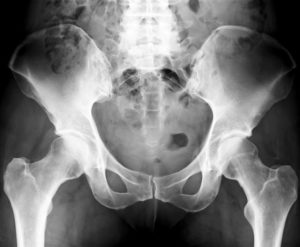

КТ позволяет визуализировать состояние костей, процедуру назначают при травмировании, болезнях суставов. Необходимо исследование и для точной диагностики нужной зоны перед оперативным вмешательством.

Нужда в диагностике Кт костей таза возникает, если наблюдаются ограниченная подвижность конечность и боли. На панорамном снимке отчетливо видны различные кости, суставы и сочленения.

На снимках можно рассмотреть кость со всех сторон, дифференцировать перелом и опухоль. Исследовать кость таза необходимо при: